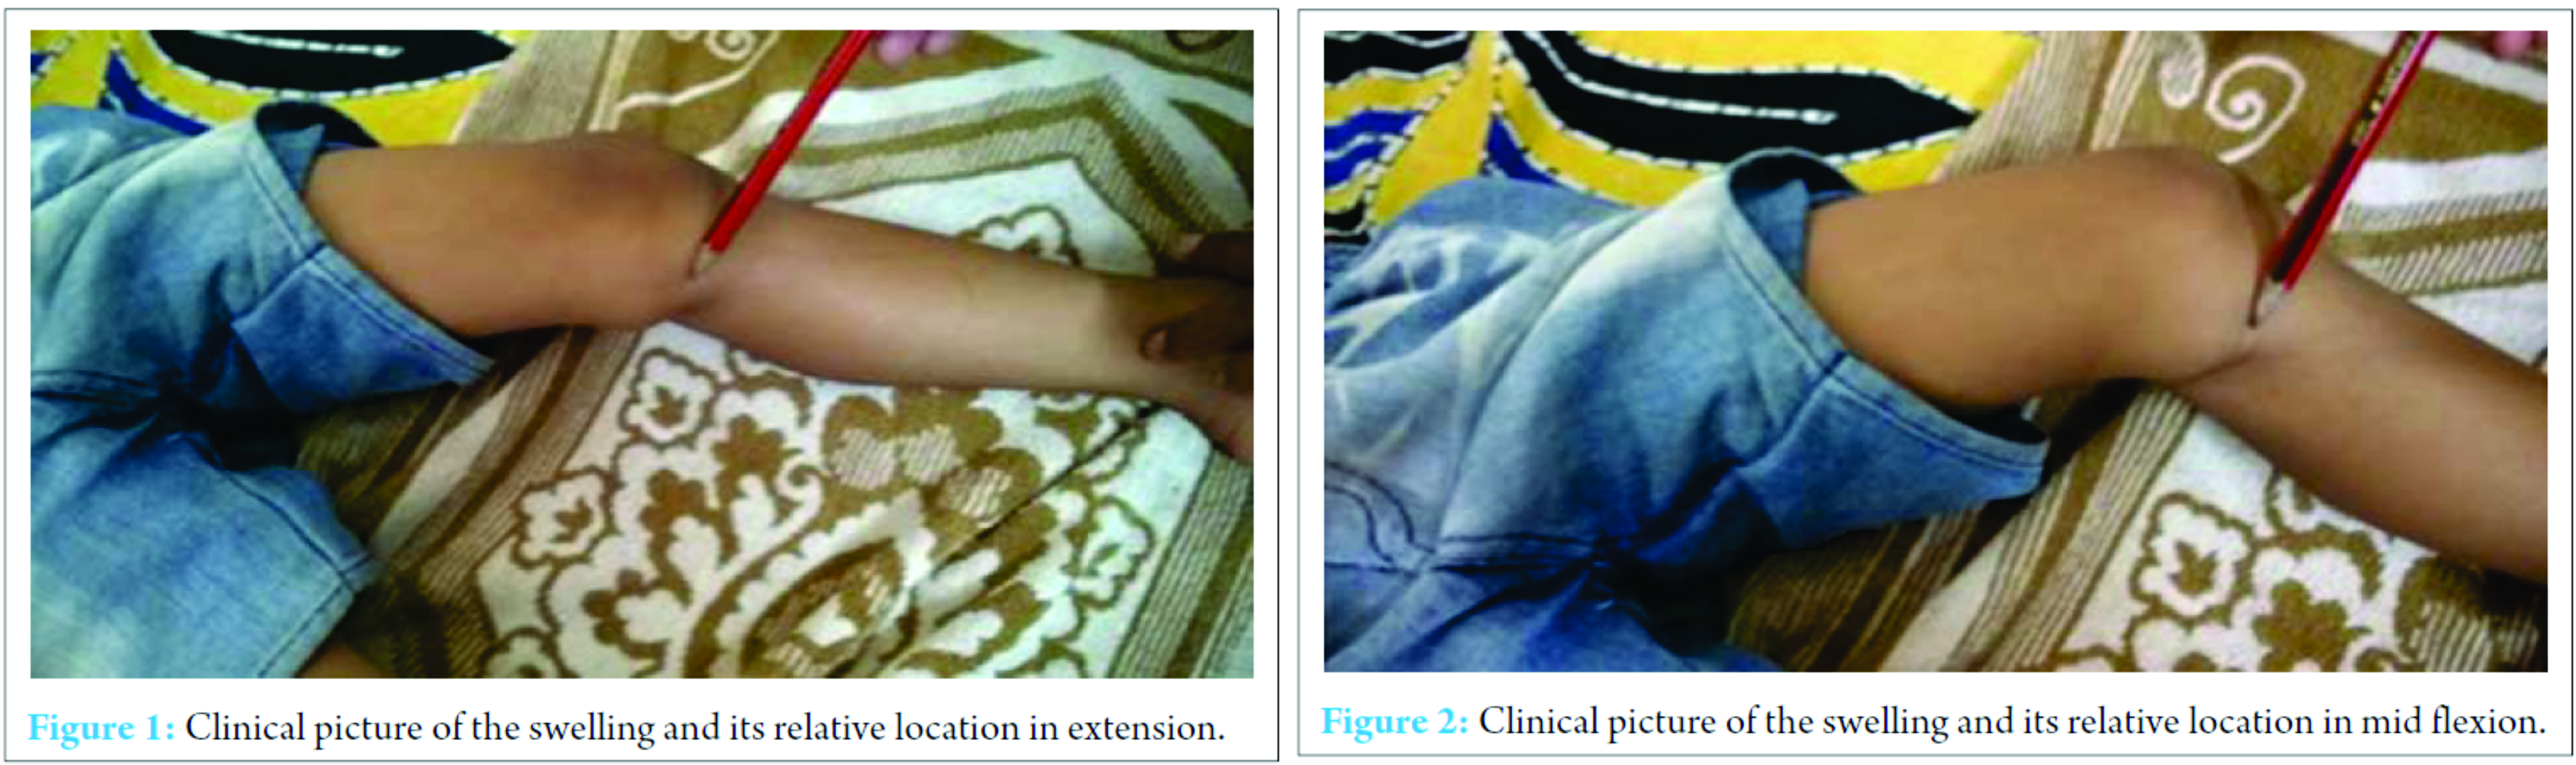

X-ray of the knee joint was unremarkable (Fig. 3, 4). Ultrasonography (USG) revealed a hypoechoic well-defined cystic lesion with clear contents is visualized on the antero-medial aspect of the left knee over the semitendinosus tendon. The lesion measures 25 mm × 10 mm. The lesion is causing splaying of the gracilis and sartorius muscles near knee; the lesion extends lower down and posteriorly and appears to fuse close to pes anserine insertion near the pulsation of the medial geniculate artery (Fig. 5, 6). Doppler USG showed no evidence of vascular involvement.